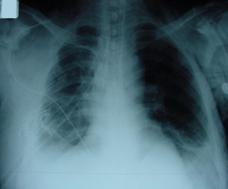

Pneumotorace simplu stang Pneumotorace

simplu stang

Pneumotorace